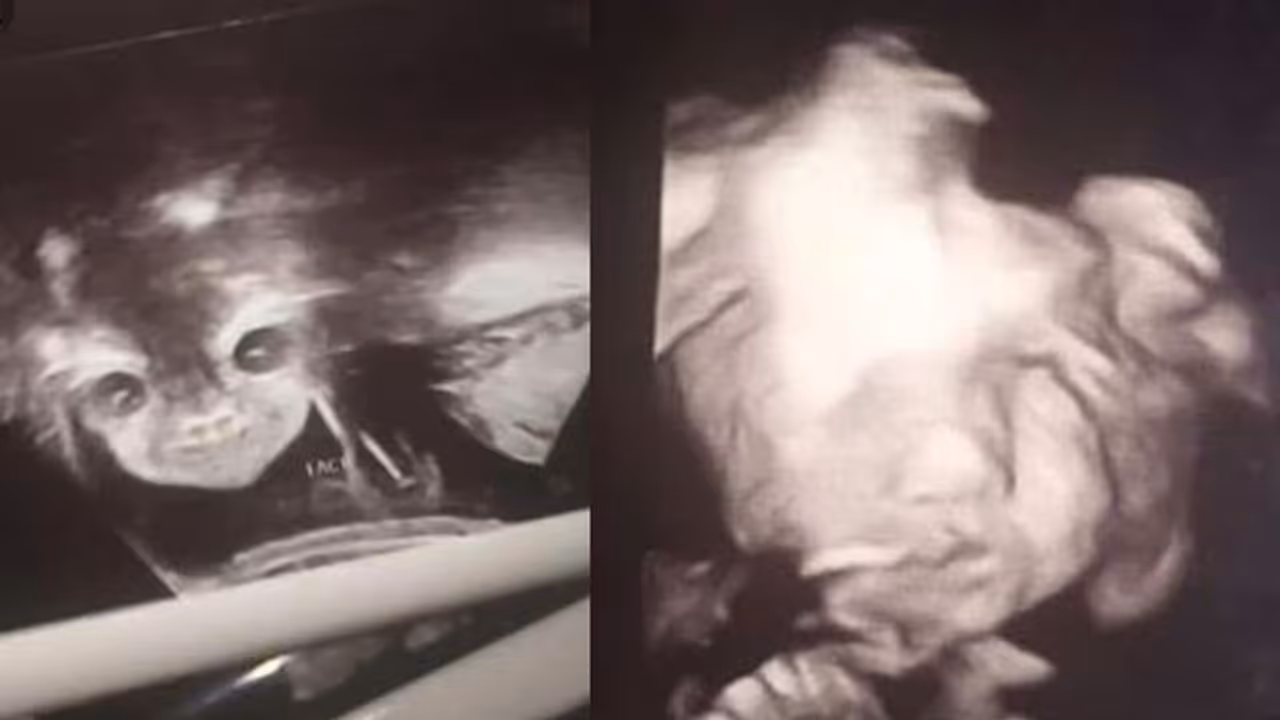

അയന്ന കാരിംഗ്ടൺ എന്ന 17കാരി സ്കാൻ ചെയ്യുന്നതിനിടെ കുഞ്ഞിന്റെ മുഖമൊന്ന് കാണാൻ സ്ക്രീനിലേക്ക് നോക്കി. അയന്ന ശരിക്കുമൊന്ന് ഞെട്ടിപ്പോയി. വയറ്റിൽ കിടക്കുന്ന കുഞ്ഞിന്റെ മുഖം പിശാചിന്റെത് പോലെയിരിക്കുന്നുവെന്ന് അയന്നയ്ക്ക് തോന്നി. 24ാം ആഴ്ച്ചത്തെ സ്കാൻ ചെയ്യുന്നതിനിടെയാണ് അതിശയിപ്പിക്കുന്ന ഈ കാഴ്ച് കാണാനായത്.

ഇത് കണ്ടപ്പോൾ തന്നെ കുഞ്ഞിന് മറ്റ് എന്തെങ്കിലും പ്രശ്നമുണ്ടോയെന്ന് അയന്ന ഡോക്ടറിനോട് ചോദിച്ചു. നിങ്ങൾ ഇതിന് ടെൻഷനടിക്കേണ്ട ആവശ്യമില്ല, നിങ്ങൾക്ക് തോന്നുന്നതാണ്. വളരെ ആരോഗ്യമുള്ള ഒരു കുഞ്ഞിനെയാണ് നിങ്ങൾക്ക് കിട്ടാൻ പോകുന്നതെന്ന് ഡോക്ടർ അയന്നയോട് പറഞ്ഞു. കുഞ്ഞിന്റെ മുഖം ഒരിക്കൽ കൂടി കാണണമെന്ന് അയന്ന ഡോക്ടറിനോട് പറഞ്ഞു.

ഉടൻ തന്നെ ഡോക്ടർ വയറ്റിന് മുകളിൽ ഡോപ്ലർ വയ്ക്കുകയും ആ നിമിഷം കുഞ്ഞ് ചിരിക്കുന്ന മുഖം കാണാനായെന്ന് അയന്ന പറയുന്നു. സ്കാൻ കോപ്പിയുടെ ഫോട്ടോകൾ അയന്ന ഫേസ്ബുക്കിൽ ഷെയർ ചെയ്യുകയായിരുന്നു. യുഎസിലാണ് സംഭവം. കുഞ്ഞ് വയറ്റിൽ കിടന്ന് കാണിക്കുന്ന വികൃതികൾ സന്തോഷത്തോടെ ആസ്വാദിക്കുകയാണെന്ന് അയന്ന പറഞ്ഞു.